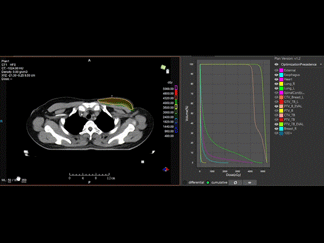

Sistemul inteligent EPID QA permite realizarea eficientă, precisă și ușor de utilizat a verificărilor de calitate pentru echipamente (Machine QA) și planuri de tratament (Plan QA), precum și monitorizarea în timp real a dozei în 2D și reconstrucția 3D a dozei administrate.

2D in vivo: monitorizarea și avertizarea în timp real a dozei pe parcursul tratamentului.

3D in vivo: reconstrucția tridimensională a distribuției dozei după finalizarea tratamentului.

Acest sistem asigură acuratețe maximă în administrarea radioterapiei și menținerea celor mai înalte standarde de siguranță pentru pacient.